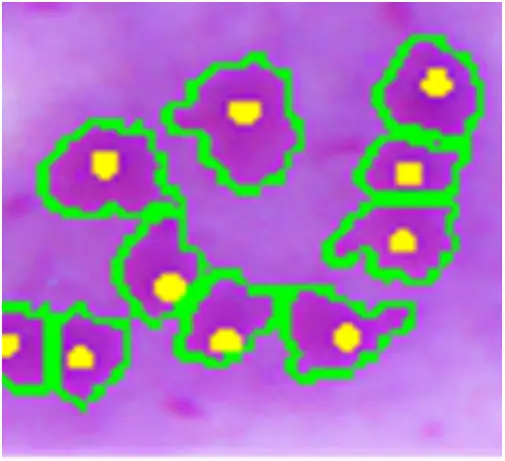

利什曼原虫的无鞭毛体是椭圆形的寄生虫,长约二到四微米,具有一个偏心的细胞核和副核动基体。它们可以在巨噬细胞的细胞质内或细胞外被发现,常常呈现出"蜂群"样的排列。这是诊断利什曼病的关键形态学特征。